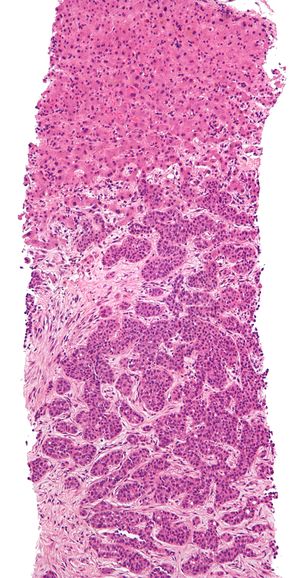

الخزعة biopsy تطلق على الجزيء المنتزع من الجسم الحي لدراسته نسجياً بغية تحديد مدى وطبيعة التبدلات المرضية فيه للمساعدة على وضع تشخيص الحالة المرضية وتدبيرها بالتالي.

يمكن تصنيف هذه الأنواع بحسب الغاية التي تجرى لها الخزعة أو بحسب طريقة إجرائها. فمنها ما يؤخذ جراحياً بغية التشخيص النسيجي، وتكون إما جزئية وإما استئصالية excisional حيث تشمل استئصال العضو المصاب بكامله ودراسته نسيجياً. ومنها ما يؤخذ عن طريق إبرة خاصة تغرس في العضو المصاب لأخذ جزيئة منه ودراستها، ويتم ذلك إما مباشرة أو بعد تصويب الإبرة نحو الآفة المشبوهة بتصويرها بالأمواج فوق الصوتية أو بالتصوير الطبقي المحوري، وتسمى هذه الخزعة بالإبرة الموجهة، وكمثال على ذلك تجرى هذه الخزع في سرطانات الموثة وآفات الثدي.

كما يمكن أخذ خزع من بعض الآفات بغرس إبرة جوفاء فيها ومصّ الخلايا من خلالها للدراسة النسيجية وتسمى بالخزع الارتشافية.

ومن الخزع ما يجرى عبر المناظير المختلفة المدخلة إلى الطرق الهضمية أو البولية أو التنفسية وغيرها، وتجرى بوساطة ملاقط قاطعة أو عرى كهربائية قاطعة تدخل عبر هذه المناظير لتؤخذ الخزعة من المنطقة المشبوهة تحت النظر.